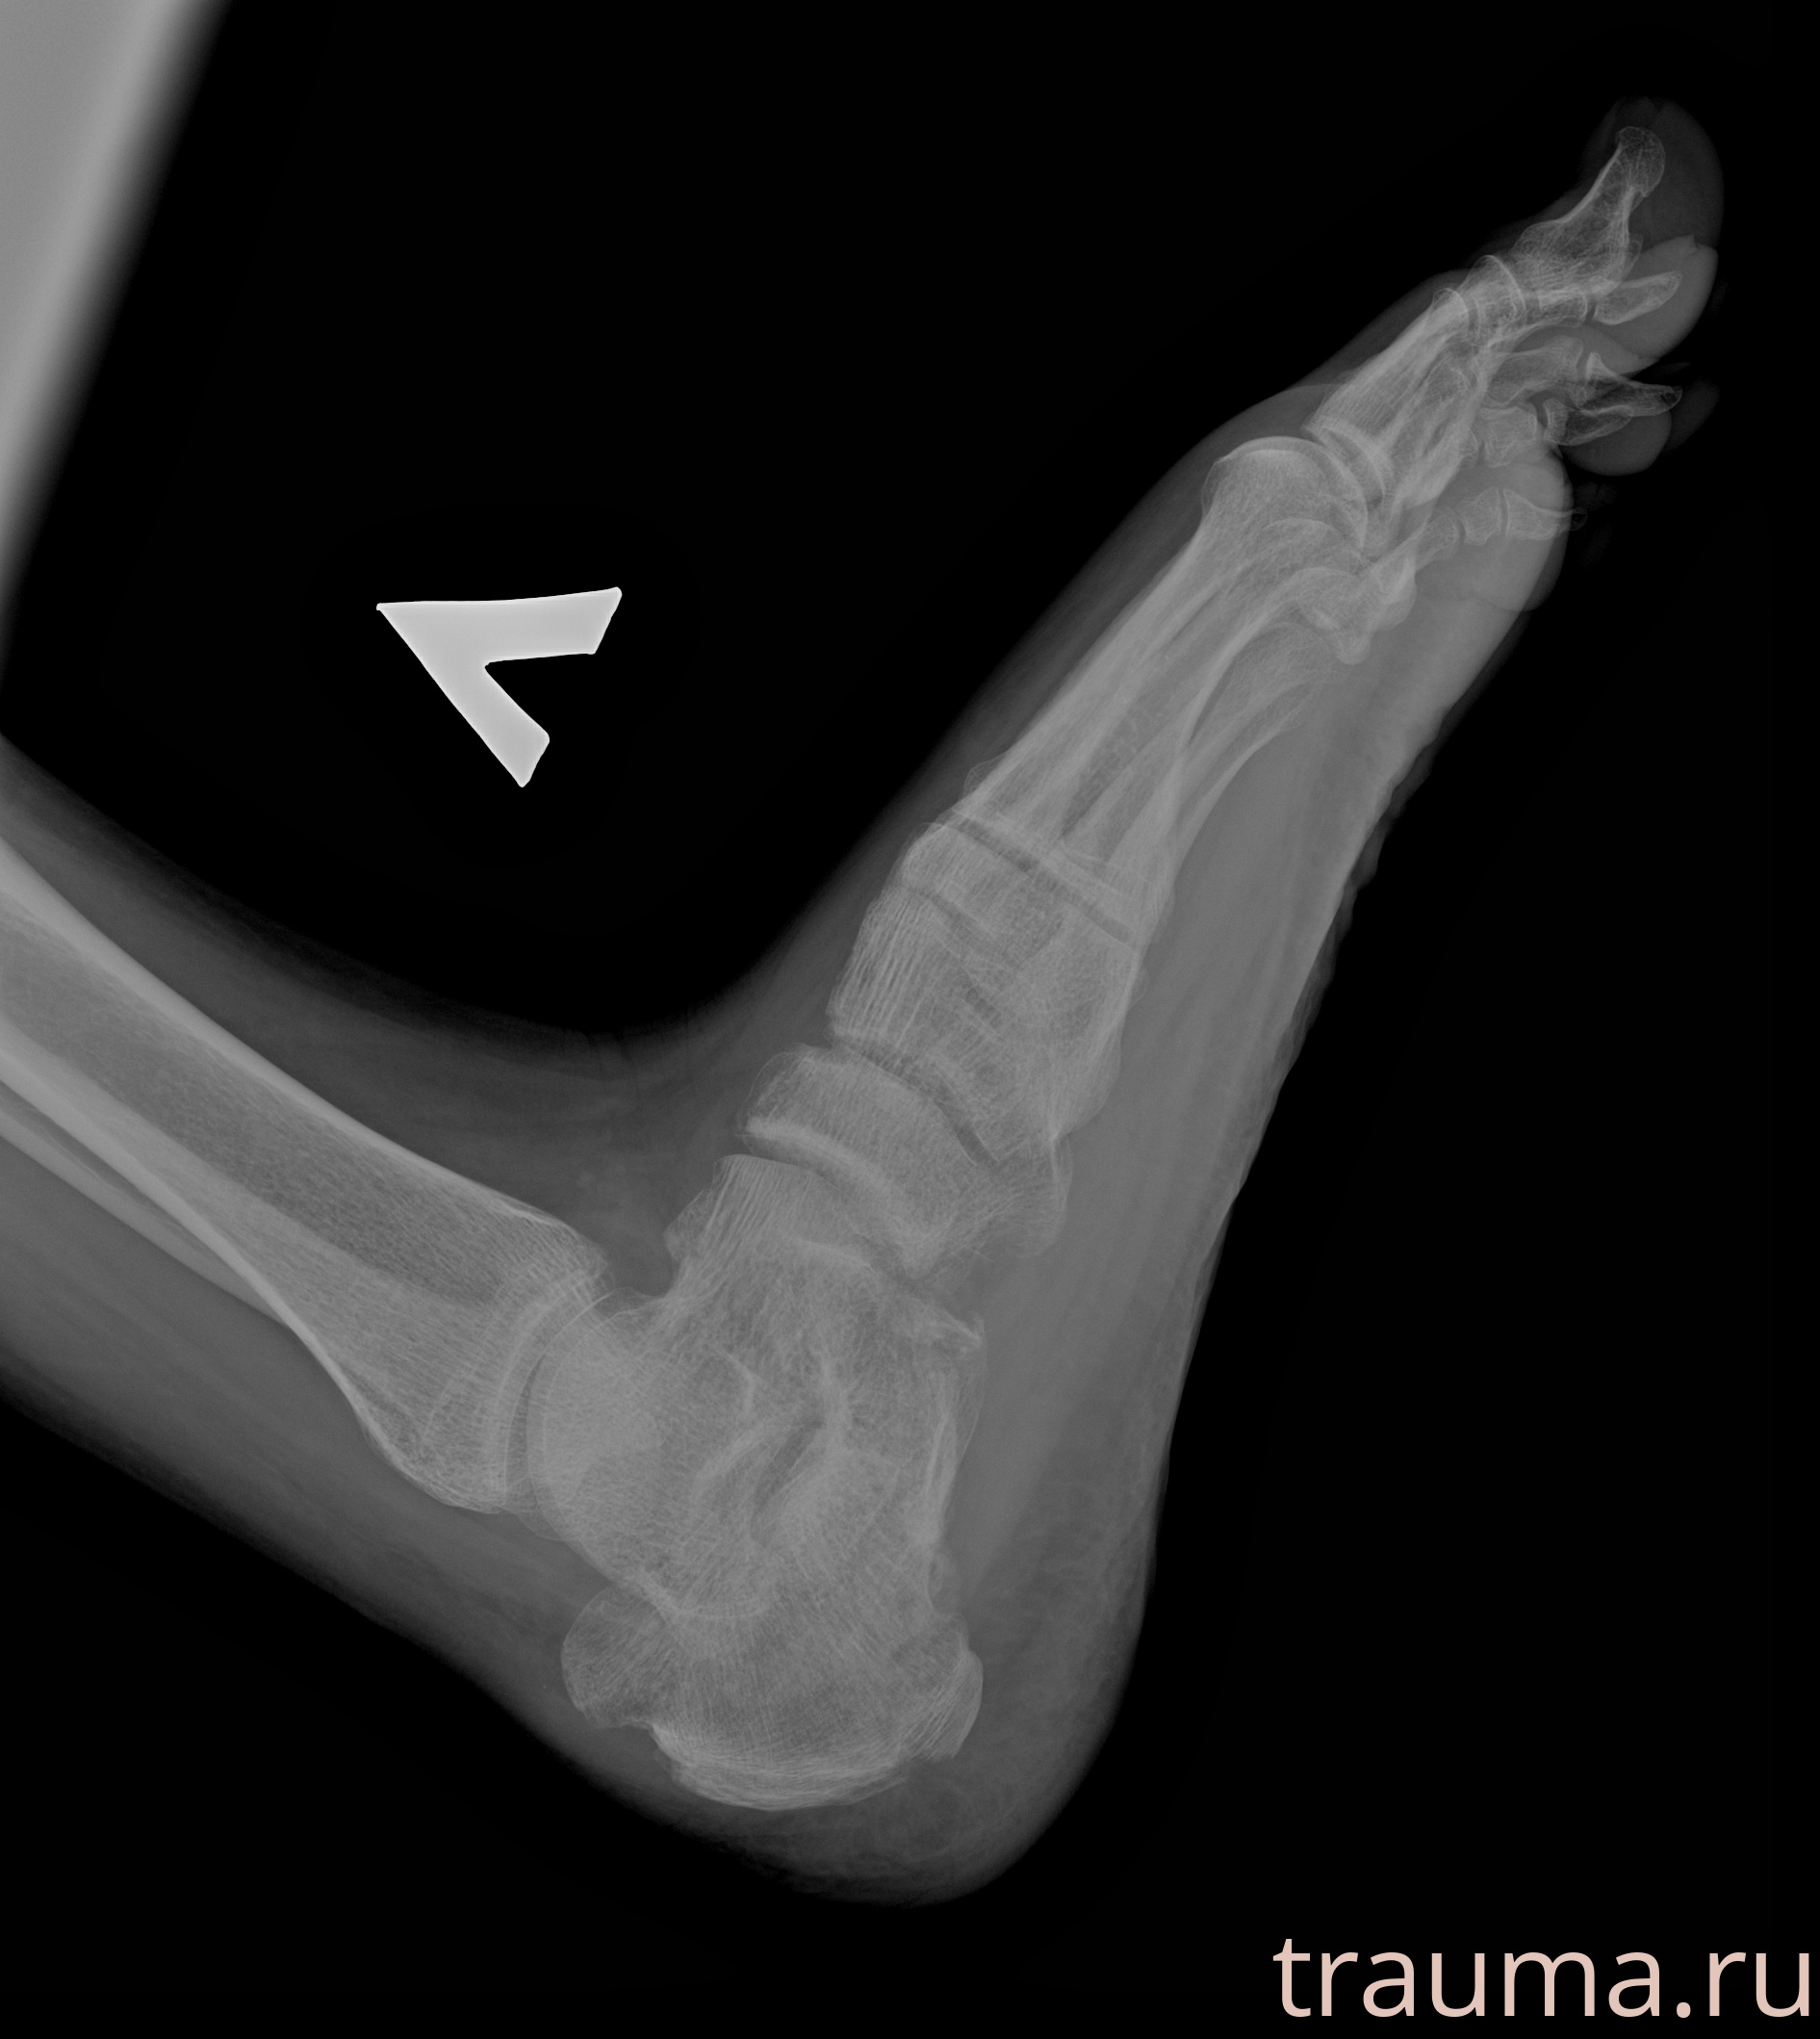

Рентген на дому: по вашему адресу приезжает врач-рентгенолог, травматолог-ортопед с мобильным рентгеновским аппаратом, проводит диагностику травмы или заболевания, делает необходимые рентгенограммы, дает рекомендации по дальнейшему лечению. Получить качественные снимки в домашних условиях возможно благодаря уникальной методике, разработанной МосРентген Центром для института  Склифосовского